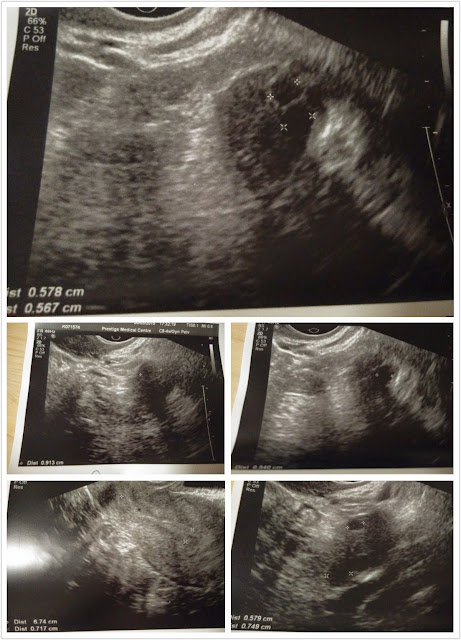

3月20日,今天預約了到診所照超聲波及抽血,

結果是用來決定打排卵針的分量。

我告訴醫生我的用意,他馬上替我照超聲波,

結果不太理想,右邊只有3個大一點的卵泡,

而左邊只有2個,醫生說比較少,情緒馬上有一點低落。

很怕到最後只抽到5個卵子。

馬上把超聲波圖片傳給周小姐,並問她打針後會否也只有5個卵子,

她説會多一點,所以我才比較安心。